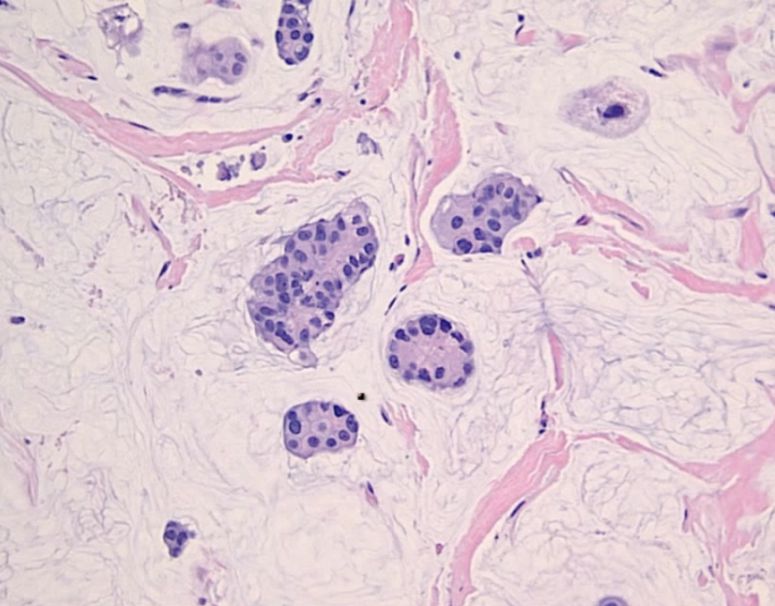

The following image represents the _____ carcinoma subtype of invasive ductal carcinoma:

The following image represents _____ carcinoma (breast):